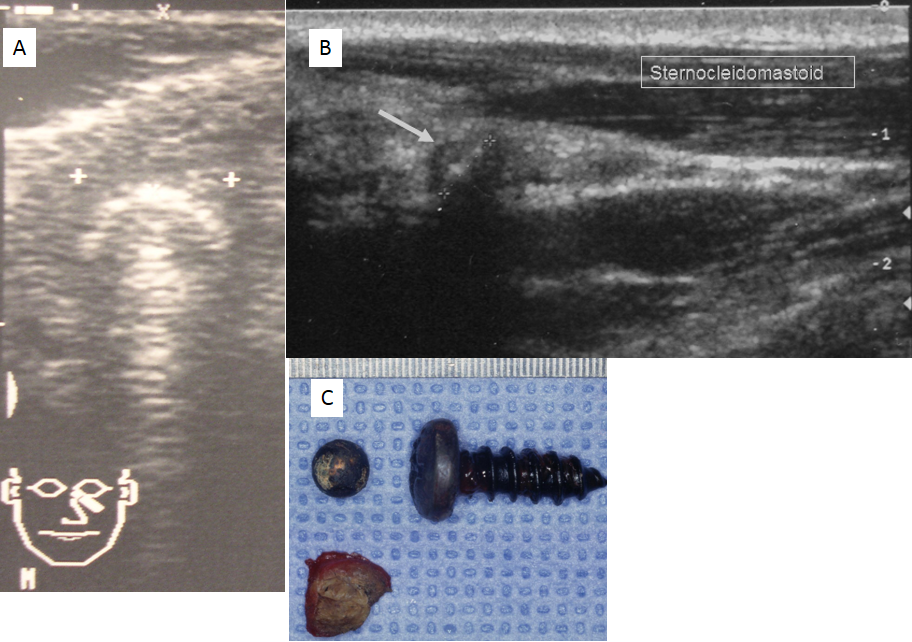

Figure 2: A. Ultrasonogram of the orbital foreign body. The skin-to-object distance is about 5 mm. The hemispheric diameter is about 9 mm. B. Ultrasonogram of the left parapharyngeal space reveals an ultrasound remitting surface in an oblique position to the surface of the applicator. Proximal to the applicator and covering the surface is a concave hypoechoic zone (arrow). C. The foreign bodies (left: airgun pellet, right: screw) and the fibrous bag that covered the screw (left below) with millimetre scale (total length of screw: 30 mm; diameter of screw head: 12 mm; pellet diameter: 9 mm).

In the left neck the foreign body was identified anterior and medial to the sternocleidomastoid muscle (Figure 2B [Fig. 2]). The foreign body was localized closely to the internal jugular vein. Ultrasound depicted the head of the screw that was measured to be of about 10 mm in diameter.

Surgery was then performed in general anaesthesia. On the left neck a skin incision was made at the anterior border of the sternocleidomastoid muscle. The screw was lying in the fat tissue surrounding the internal jugular vein and it was attached to the inner layer of the muscle. The screw was easily removed. The eye lid’s foreign body was removed after a horizontal lower eyelid incision. The spheric foreign body was embedded in a pseudocapsule. It was completely removed with this capsule (Figure 2C [Fig. 2]). Ultrasound-assisted surgical treatment planning reduced the operation time to 20 minutes. Healing was uneventful. Histology of the pseudocapsule revealed a scary tissue with strand-like calcifications, a foreign body reaction with formation of multinucleated giant-cells and a histiocyte infiltrate.